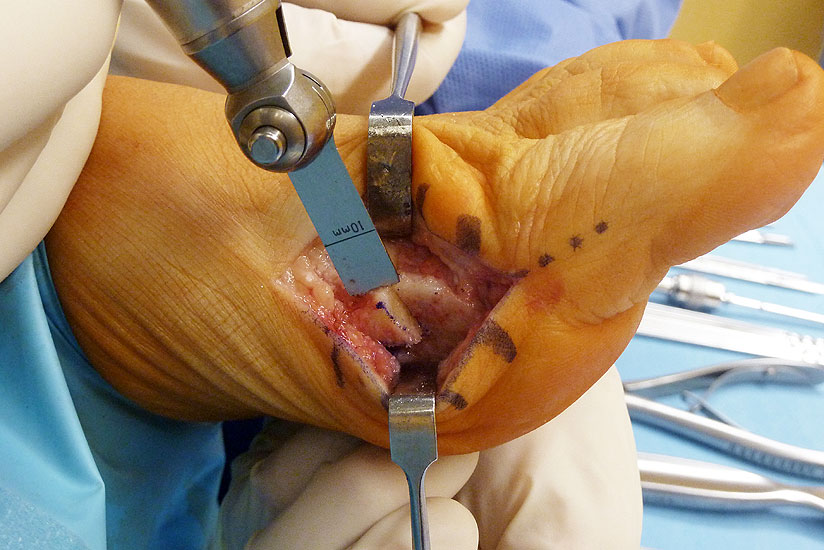

Abbildung 2

Allgemeines Fußinstrumentarium mit Pinzetten, Skalpell(en), Klemmchen, Luer, kleiner Meisel, Seidenschneider, Zange, kleine Langenbeckhaken und Hohmann-Hebel, Präparierschere, kleines Raspatorium und McGlamry Elevator (Abbildung 2)

Abbildung 3